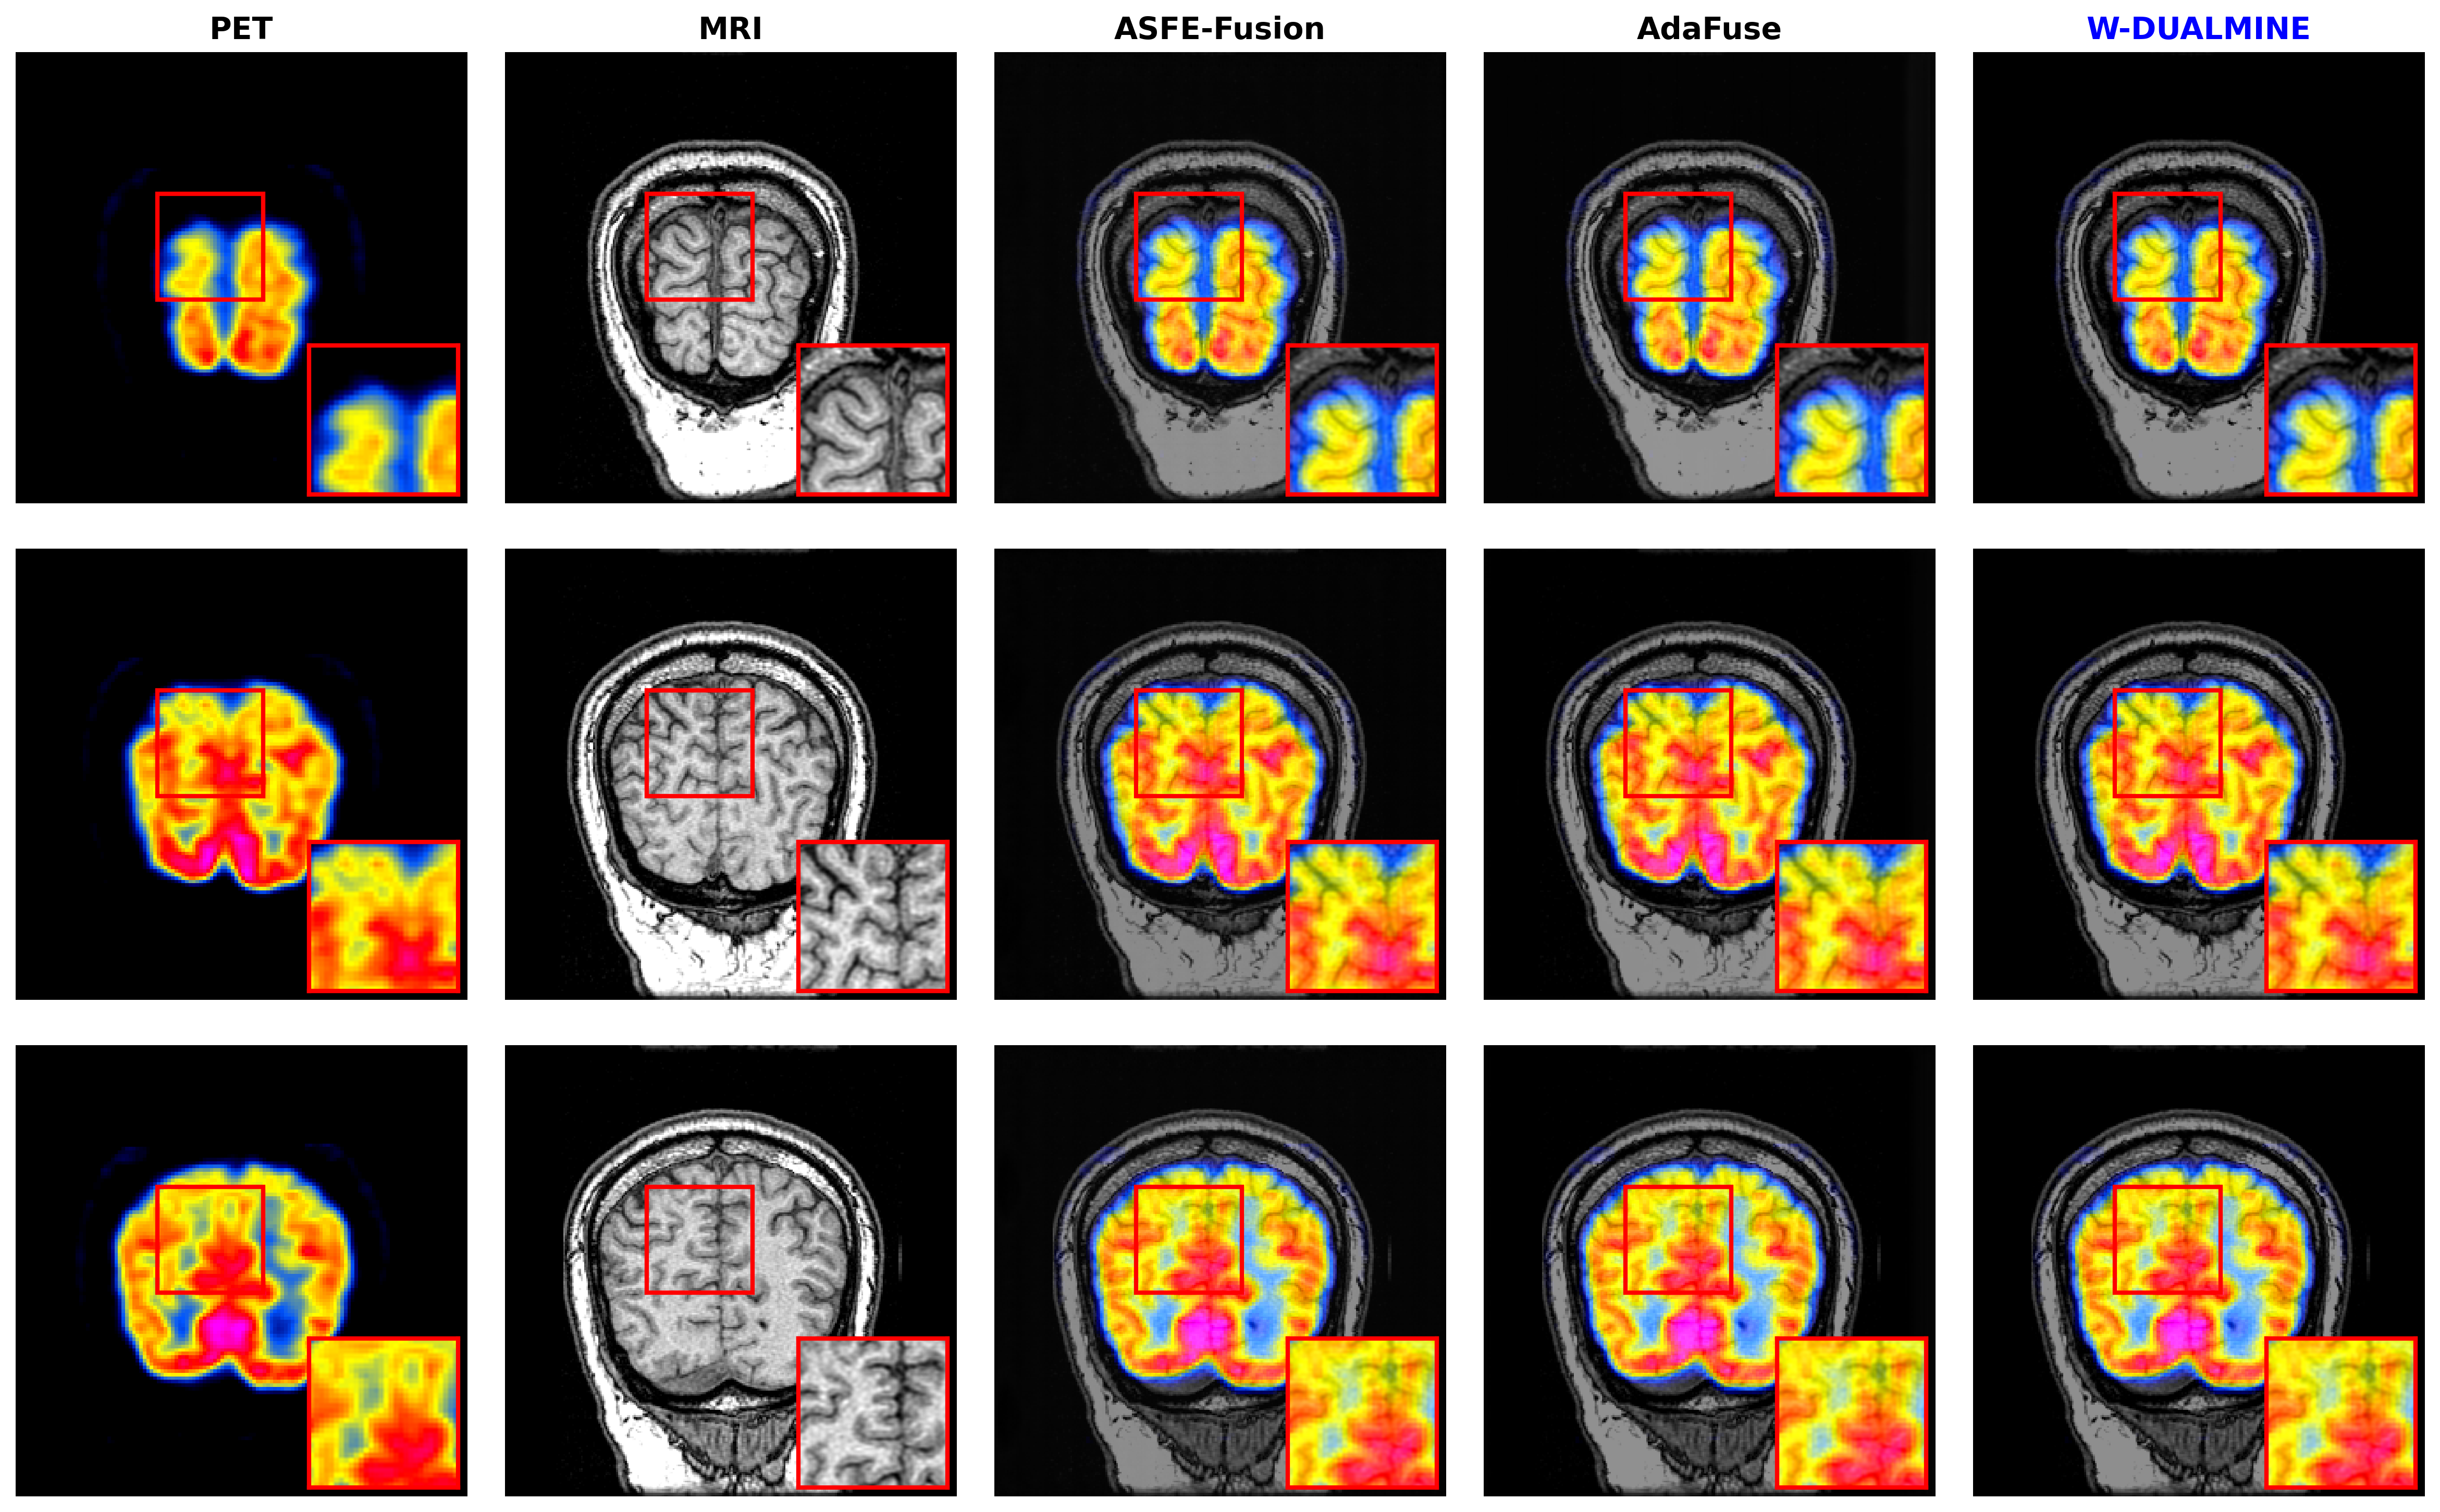

5.3.2 Results on PET–MRI Dataset

The PET–MRI dataset requires fusing low-resolution metabolic color information with high-resolution anatomical structures. Results are shown in Table 2.

Refer to caption

Figure 4: Qualitative comparison on the PET–MRI fusion task. From left to right: PET image, MRI image, ASFE-Fusion, AdaFuse, and W-DUALMINE. Highlighted regions demonstrate superior preservation of functional activity without color diffusion.

As shown in Figs. 35, W-DUALMINE produces visually superior fusion results across all modalities. The proposed method achieves better structural clarity and functional consistency than ASFE-Fusion and AdaFuse, particularly in highlighted regions.